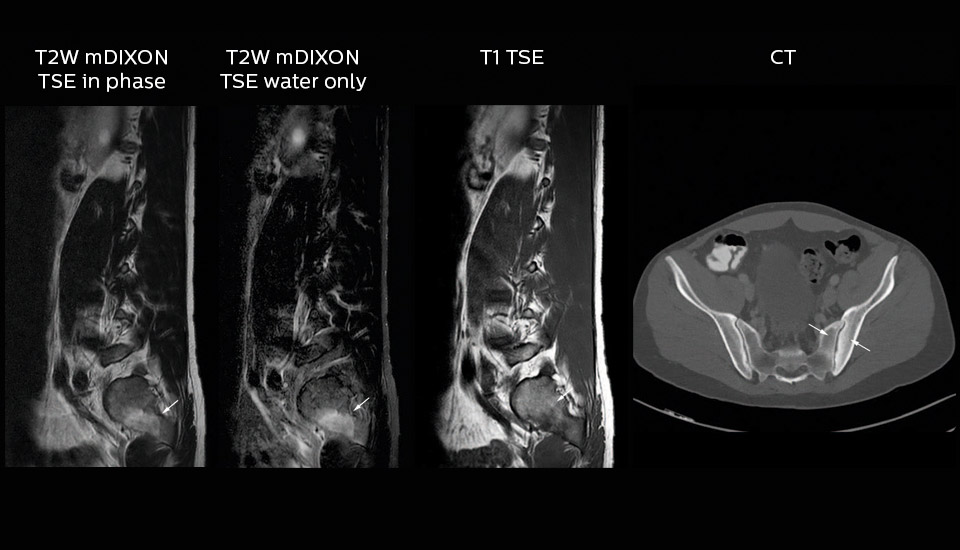

More information without extending time slot

“In our lumbar spine MRI, the value of mDIXON TSE is so obvious. Normally we perform T1 and T2 scans in sagittal and transverse orientation.It used to take too much time to add a sagittal T2 with good fat suppression.But now, using mDIXON TSE, we get the sagittal T2 fat suppressed images ‘for free’, that is: without adding time.”

“Diagnostically that is a great benefit. I sometimes see abnormalities in the fat suppressed sagittal T2 that would be quite challenging to notice in the T2 without fat suppression. There have been several diagnoses that I could make easier because of our exam setup with mDIXON TSE, such as sacrum insufficiency fractures and sacroileitis; these were more challenging with our previous exam setup.”